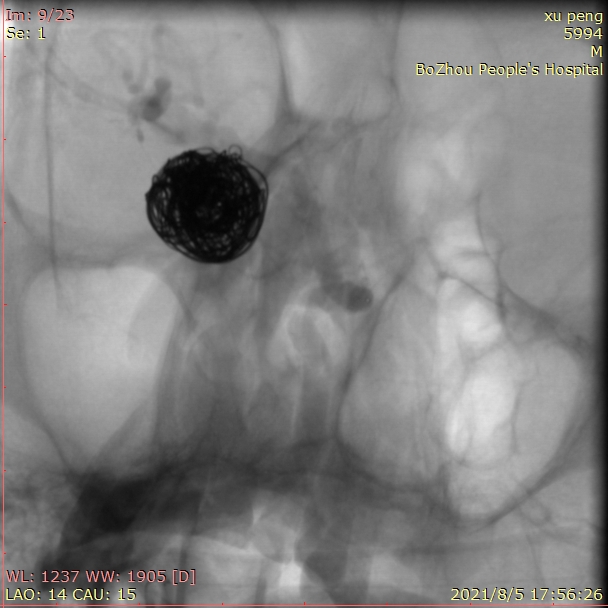

用两根微导管依次缓慢、小心填入9/30,8/30,7/20,6/20,5/10,3/8等圈,即刻造影,动脉瘤不显影,最终达到完全栓塞。

观察15分钟后再次造影,正位片。

观察15分钟后再次造影,侧位片。

载瘤动脉通畅,手术结束。

术后患者带气管插管回病房,次日病人神志清楚,四肢活动自如。